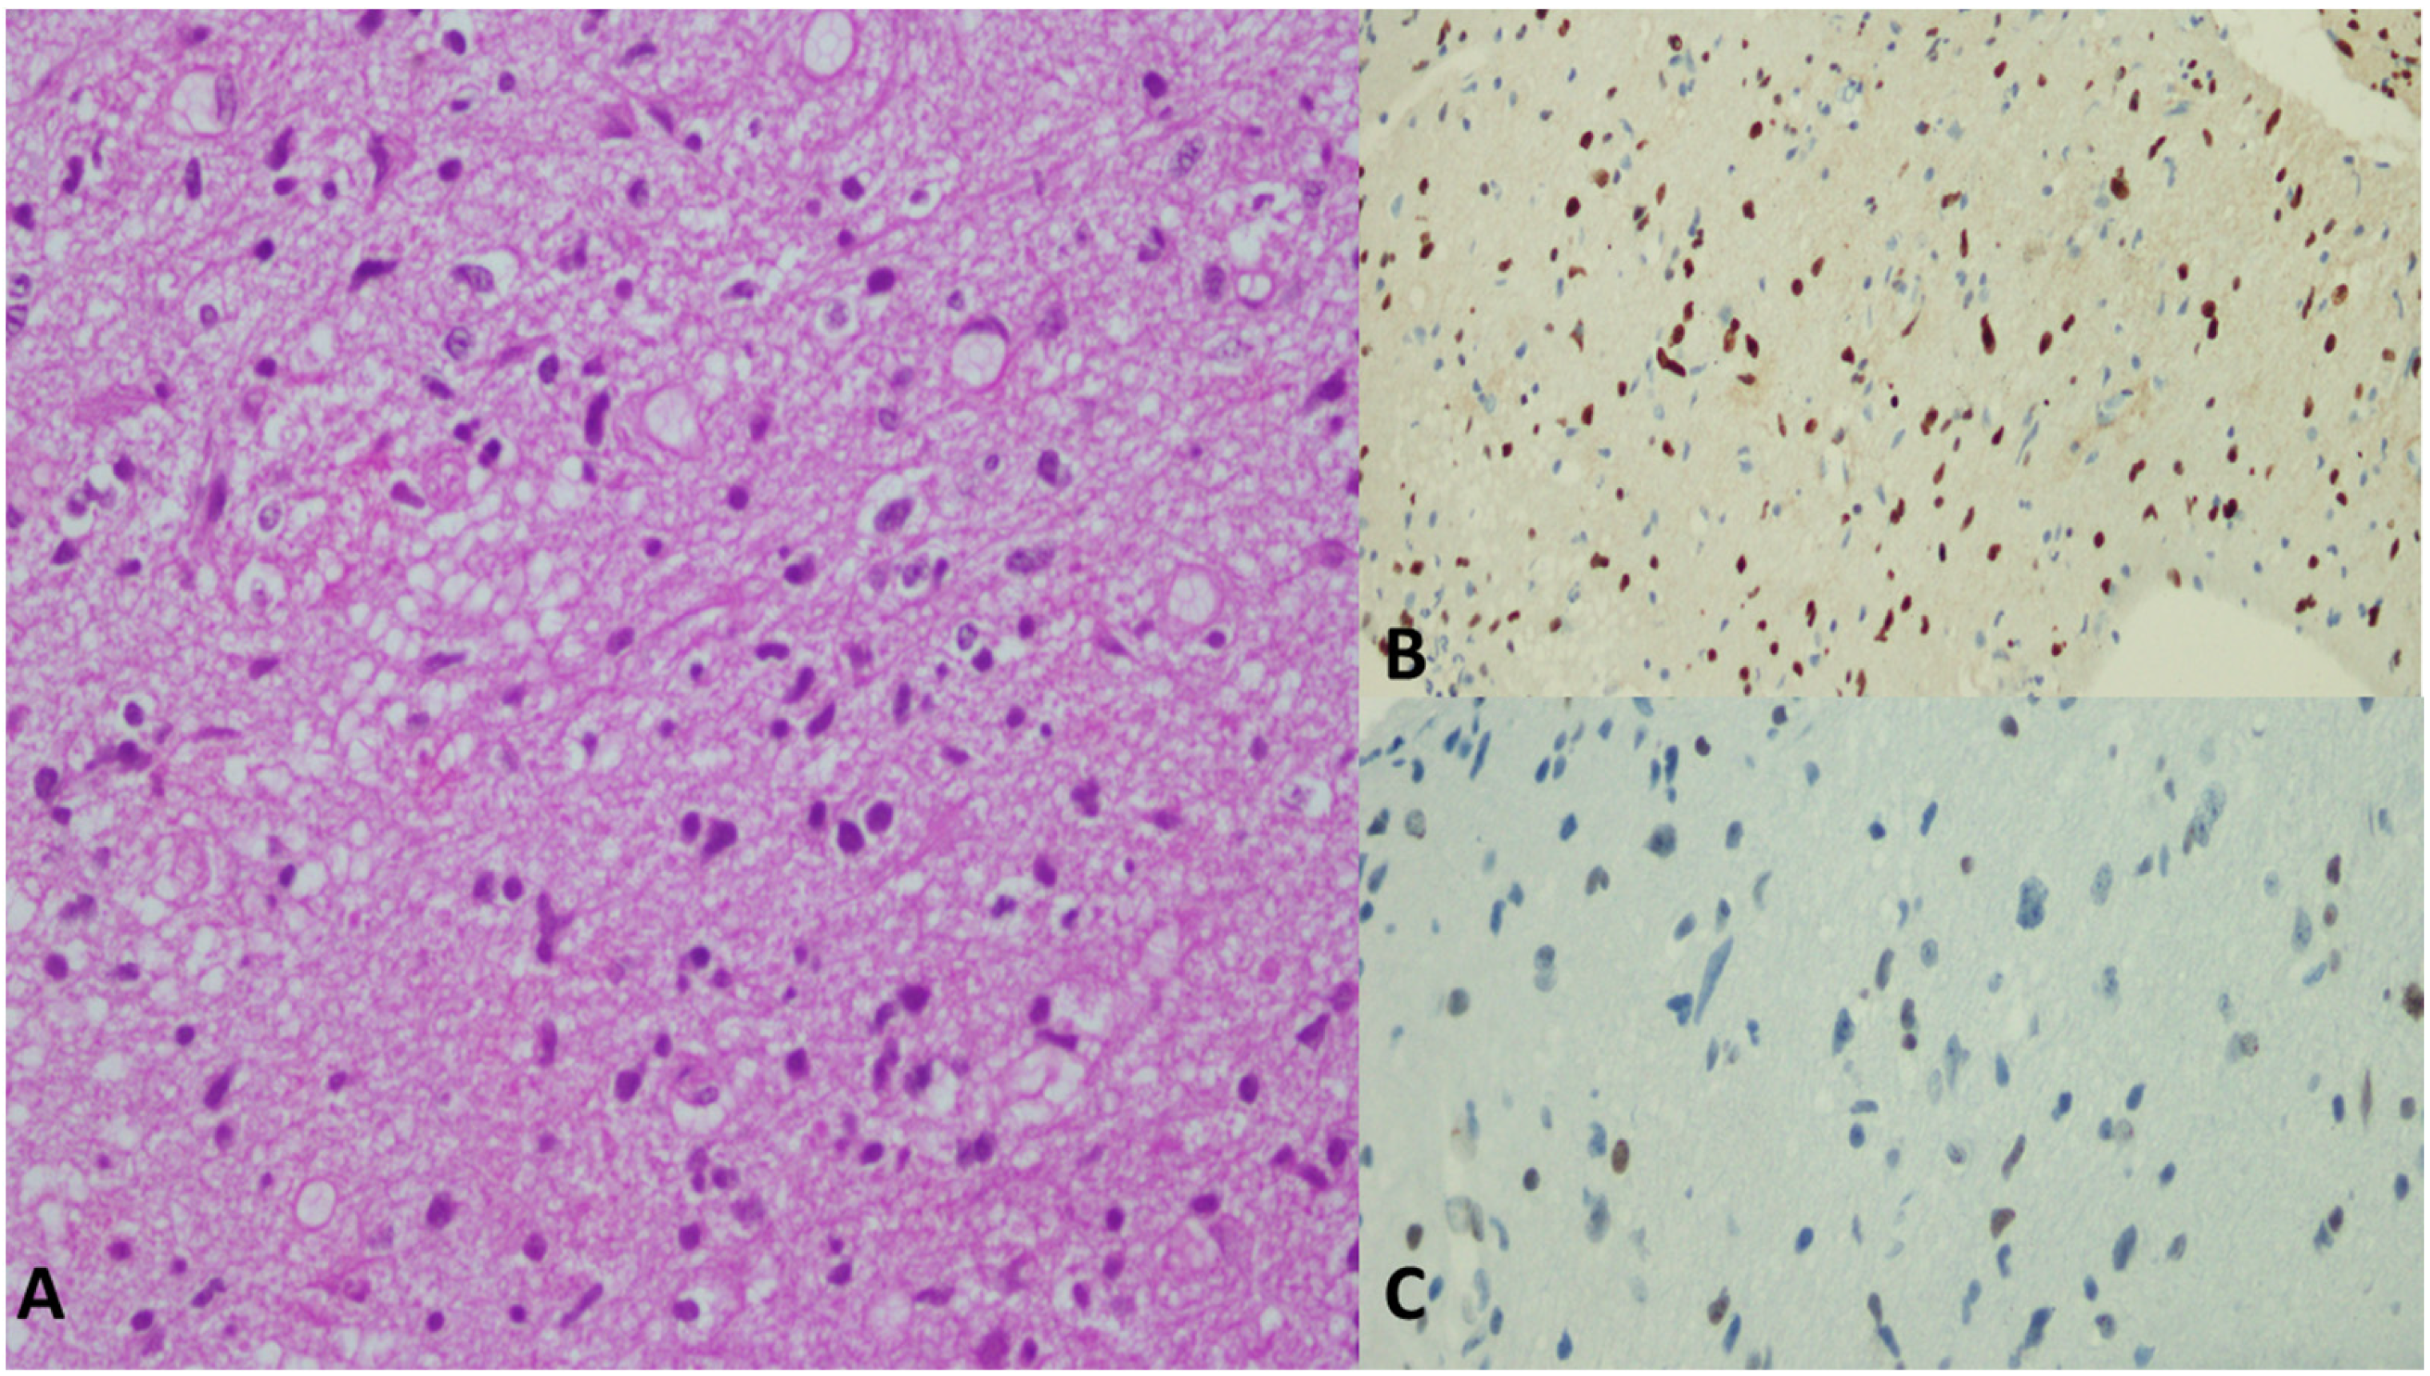

6. Histological Features